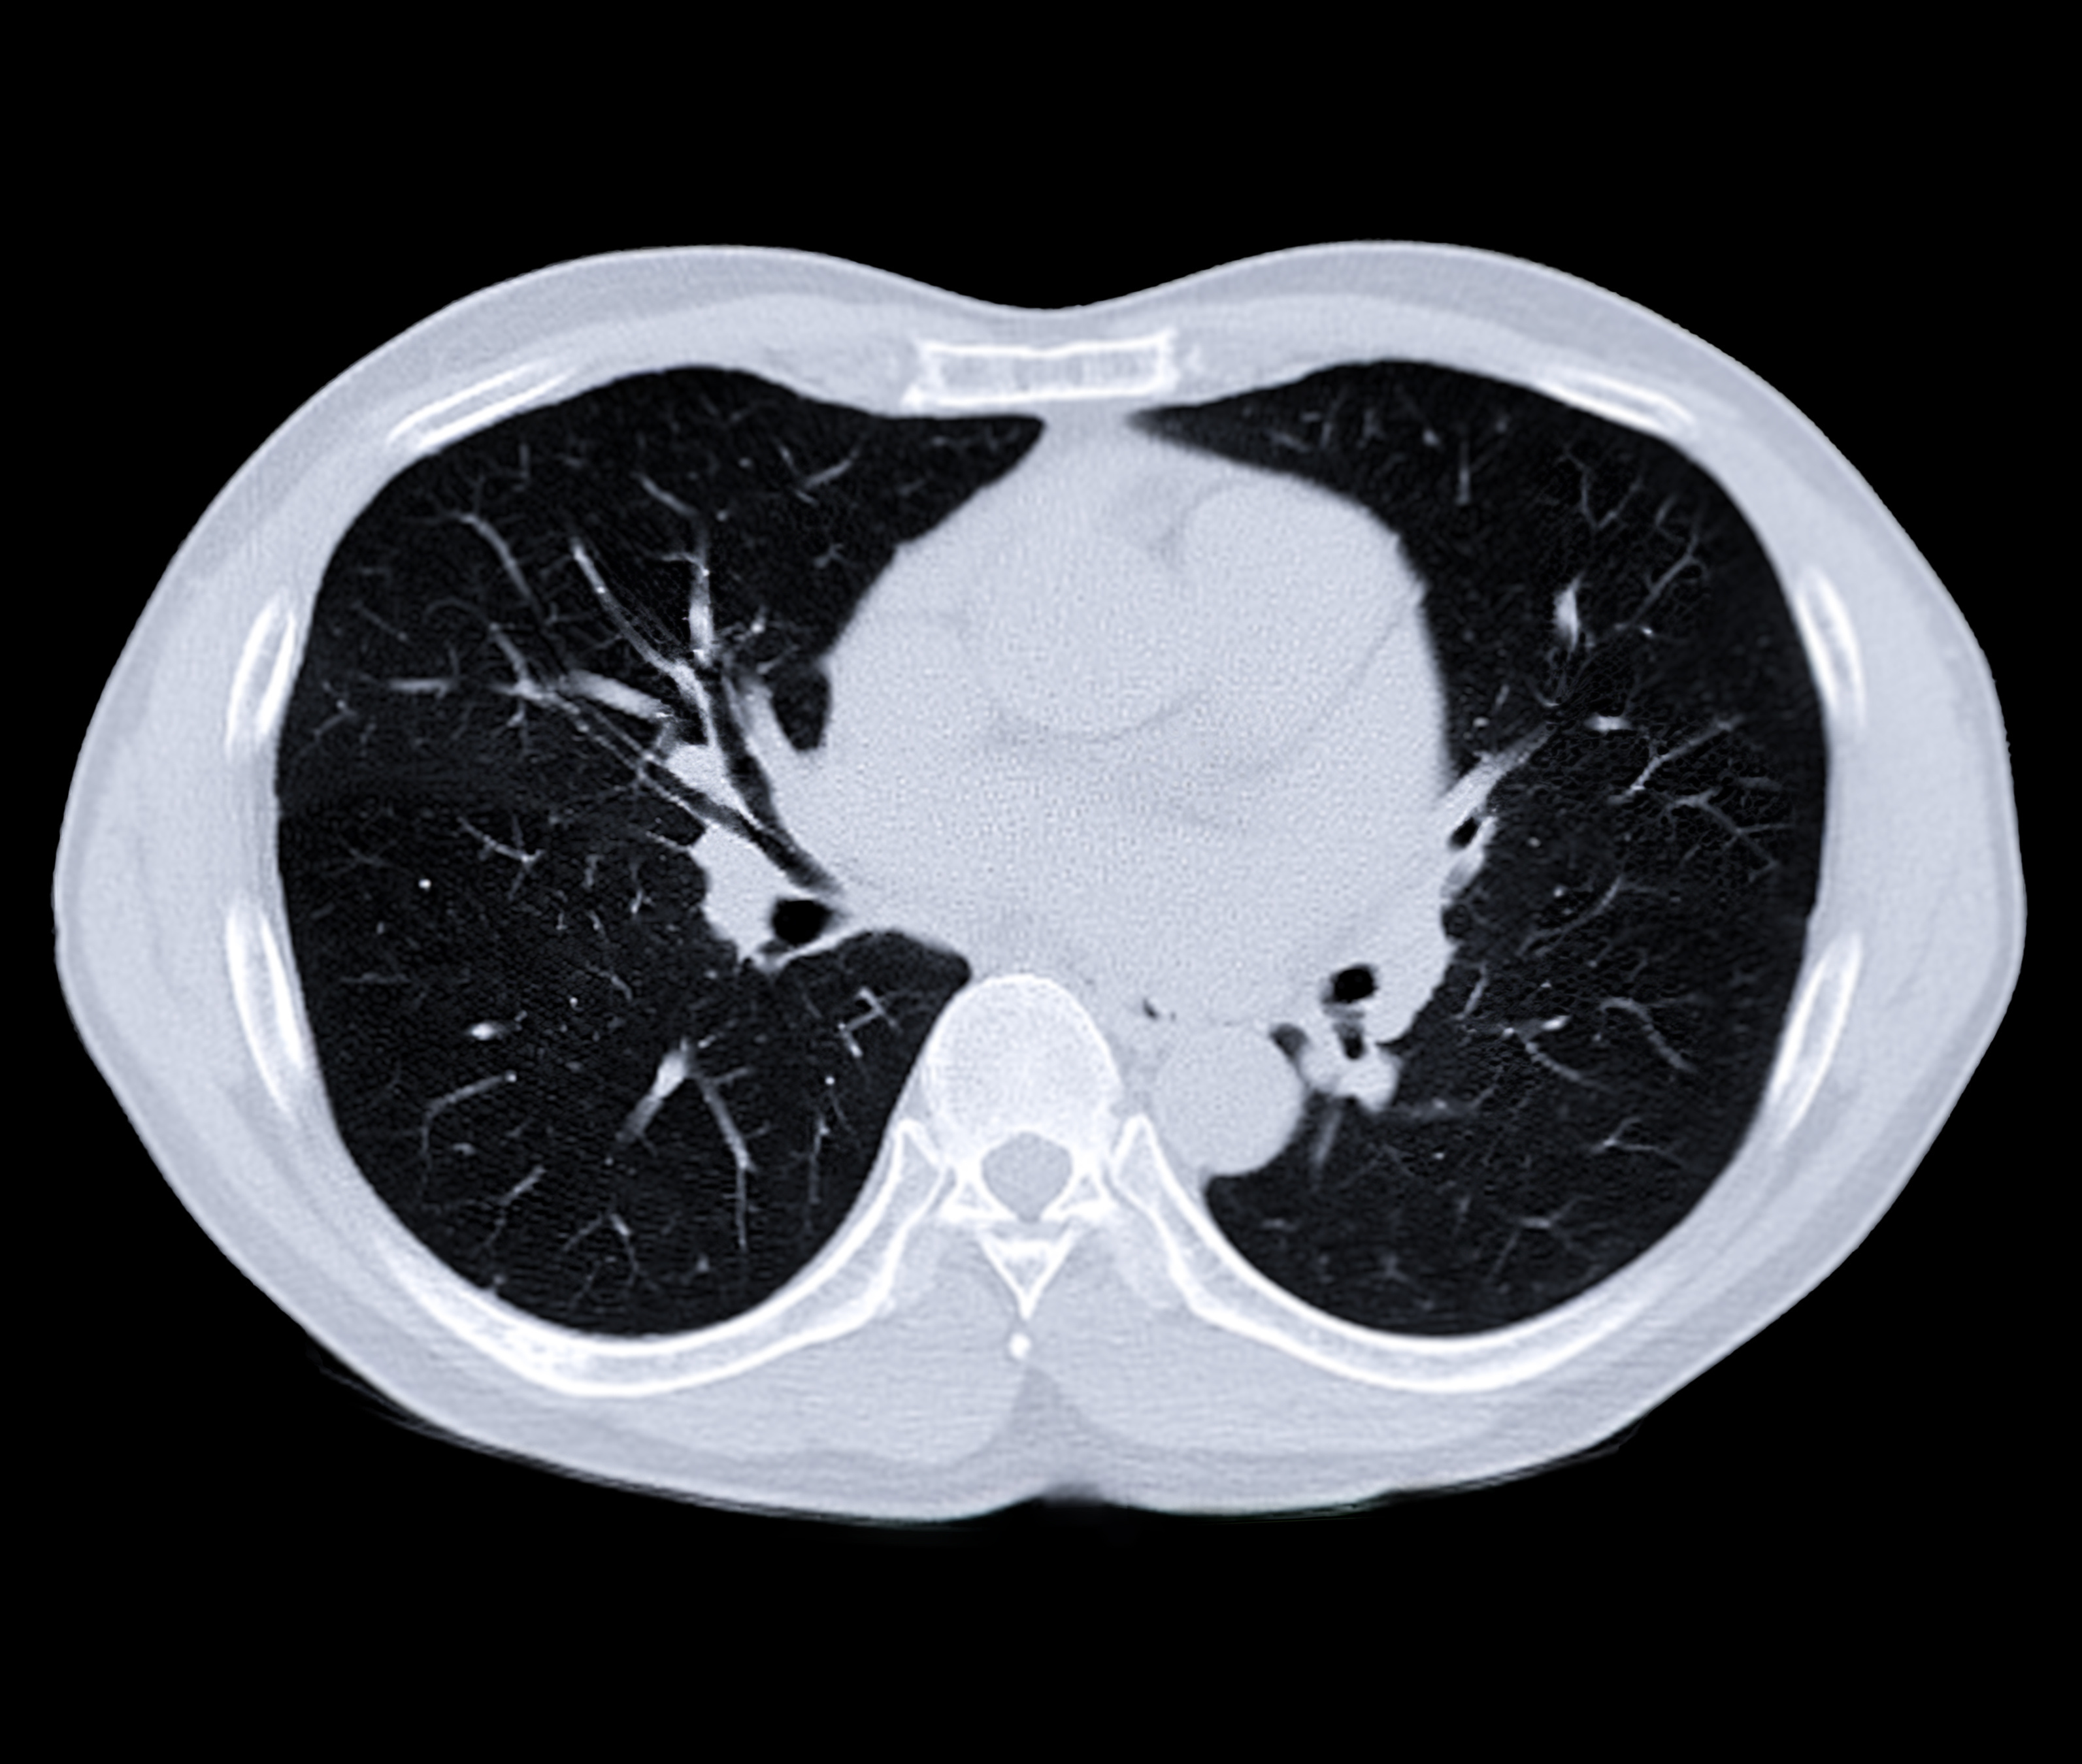

Managing Interstitial Lung Disease in ADC Clinical Trials